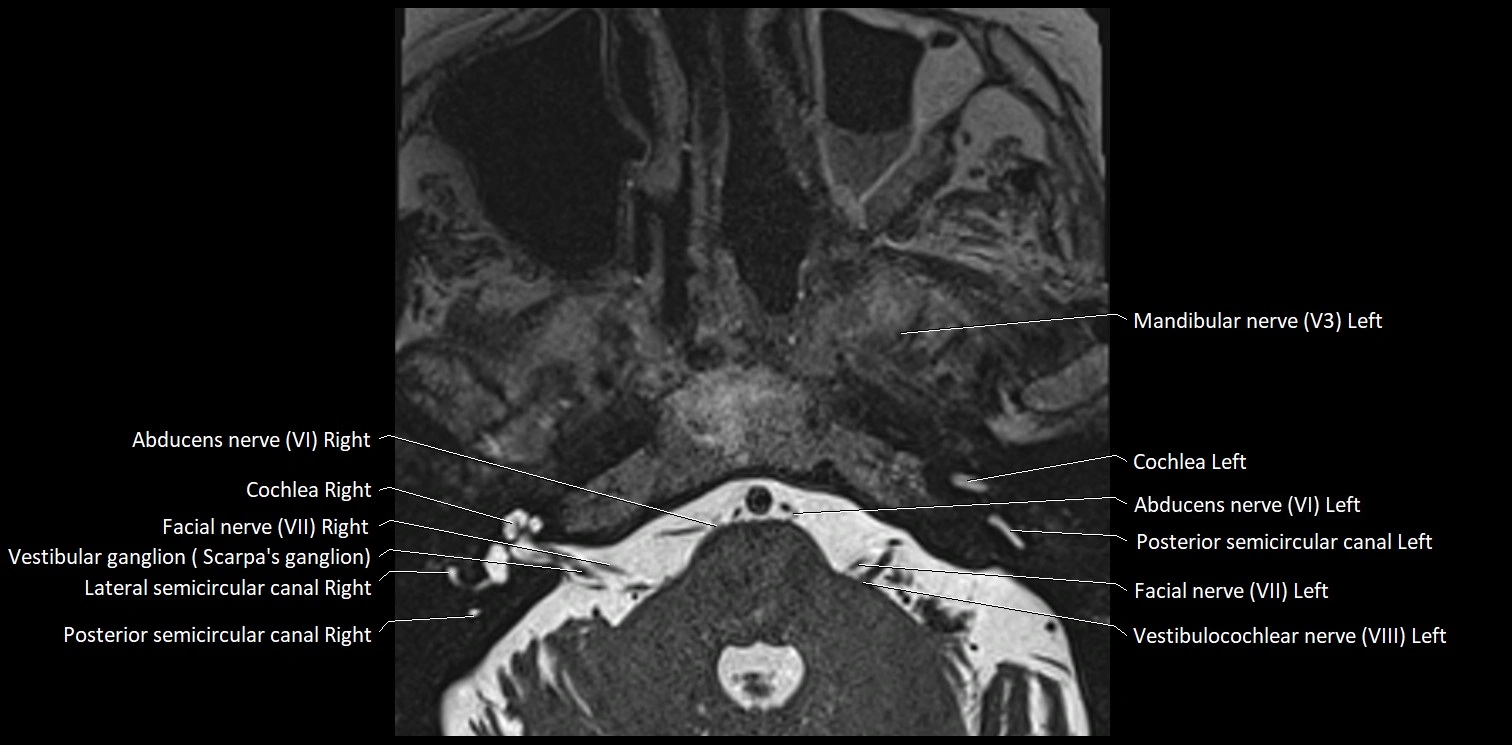

MRI Appearance

• The abducens nerve is a small, thin, linear structure

• Best visualized on high-resolution T2-weighted 3D MRI sequences (e.g., FIESTA or CISS)

• Seen as a hypointense (dark) line running from the brainstem at the pontomedullary junction, traversing the prepontine cistern, and entering Dorello’s canal under the petrosphenoidal ligament, then into the cavernous sinus, and finally the orbit

• May be challenging to visualize in standard MRI due to its small size

• Pathology may be inferred by absence, displacement, or enhancement of the nerve

MRI images

image